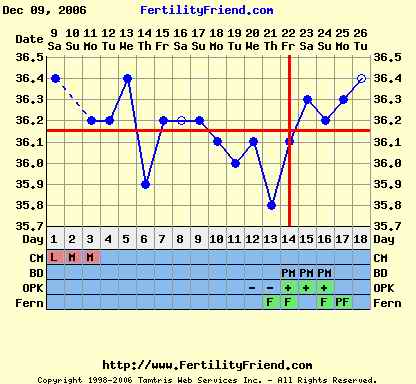

Nem tudom, hogy ez normális-e, miközben minden hormonom rendben, és a hőgörbe mutat pé-t. Meg van pozitív LH tesztem is...

Gaby: a Te görbéd elég cikkcakkos, szerintem később pé-zel...Végülis hathatott a párodnál már a gyógyszer, ha nem is drasztikusan, de már jobbak lehetnek az eredményei...